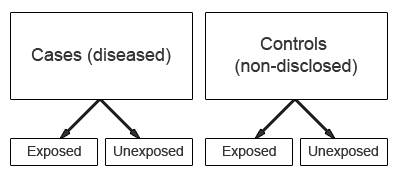

The “cases” are the individuals with the disease or condition under study, and the “controls” are similar individuals without the disease or condition of interest.

Case-control studies start with the identification of a group of cases (individuals with a particular health outcome) in a given population and a group of controls (individuals without the health outcome) to be included in the study.

In a case-control study the prevalence of exposure to a potential risk factor(s) is compared between cases and controls. If the prevalence of exposure is more common among cases than controls, it may be a risk factor for the outcome under investigation. A major characteristic of case-control studies is that data on potential risk factors are collected retrospectively and as a result may give rise to bias. This is a particular problem associated with case-control studies and therefore needs to be carefully considered during the design and conduct of the study.

Selection of controls A particular problem inherent in case-control studies is the selection of a comparable control group. Controls are used to estimate the prevalence of exposure in the population which gave rise to the cases. Therefore, the ideal control group would comprise a random sample from the general population that gave rise to the cases. However, this is not always possible in practice. The goal is to select individuals in whom the distribution of exposure status would be the same as that of the cases in the absence of an exposure disease association. That is, if there is no true association between exposure and disease, the cases and controls should have the same distribution of exposure. The source of controls is dependent on the source of cases. In order to minimize bias, controls should be selected to be a representative sample of the population which produced the cases. For example, if cases are selected from a defined population such as a GP register, then controls should comprise a sample from the same GP register.

3. Analysis of case-control studies

The odds ratio (OR) is used in case-control studies to estimate the strength of the association between exposure and outcome. Note that it is not possible to estimate the incidence of disease from a case control study unless the study is population based and all cases in a defined population are obtained.

The results of a case-control study can be presented in a 2x2 table as follow:

The odds ratio is a measure of the odds of disease in the exposed compared to the odds of disease in the unexposed (controls) and is calculated as: